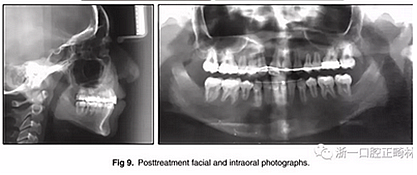

兩年半后,在上下牙弓上均實(shí)現(xiàn)了間隙關(guān)閉,并且使用0.017×0.025英寸的不銹鋼弓絲進(jìn)行咬合精細(xì)調(diào)整(圖8)。去除托槽后,上下頜采用舌側(cè)弓進(jìn)行保持(圖9)。

總體治療目標(biāo)已經(jīng)實(shí)現(xiàn)。病人的笑容和輪廓有所改善。咬合關(guān)系為I類磨牙關(guān)系,牙列整齊,牙尖交錯(cuò)關(guān)系良好。反合和中線偏移得以矯正,并實(shí)現(xiàn)了正常的覆蓋和覆合。上下牙弓的擁擠問題完全解決,并且完成后全景片顯示良好的牙根傾斜度。疊加顯示良好的縱向和垂直控制(ANB,3.5°; SN / GoMe,42.5°)和矯正上下頜前牙傾斜度(1 / SN,96°; IMPA,87°)(圖10 ; 表)。

在治療結(jié)束時(shí)沒有觀察到顳下頜關(guān)節(jié)紊亂的體征或癥狀,但發(fā)現(xiàn)了輕微的牙根吸收以及裂隙區(qū)域的骨頭輕度丟失。

治療持續(xù)3年,患者始終保持積極和合作??谇恍l(wèi)生很好。患者和她的父母都對(duì)結(jié)果感到滿意。經(jīng)過24個(gè)月的保持后,咬合保持得很好(圖11 ; 圖12)。在上牙弓中,應(yīng)用固定舌側(cè)保持器以防止任何復(fù)發(fā)傾向。在下牙弓中,治療后拔除第三磨牙。